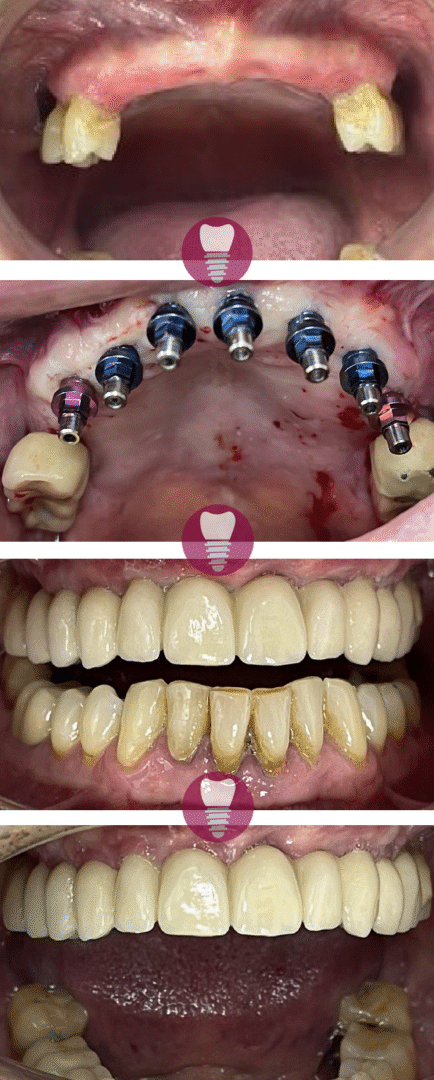

Este caso clínico muestra un tratamiento de restauración completa de la dentadura superior. Este tipo de intervención es ideal para pacientes que presentan una pérdida significativa de piezas dentales en la arcada superior o que tienen dientes gravemente dañados debido a caries avanzadas, desgaste, o problemas periodontales.

En este tratamiento, se emplea una prótesis sobre barra en implantes, proporcionando una solución estable y estética que permite recuperar la funcionalidad y la apariencia de la sonrisa. Este enfoque no solo mejora la capacidad de masticación del paciente, sino que también refuerza la estructura facial y restaura la confianza en su aspecto.

Gracias a la planificación digital y los materiales de alta calidad utilizados, el resultado es duradero y natural.